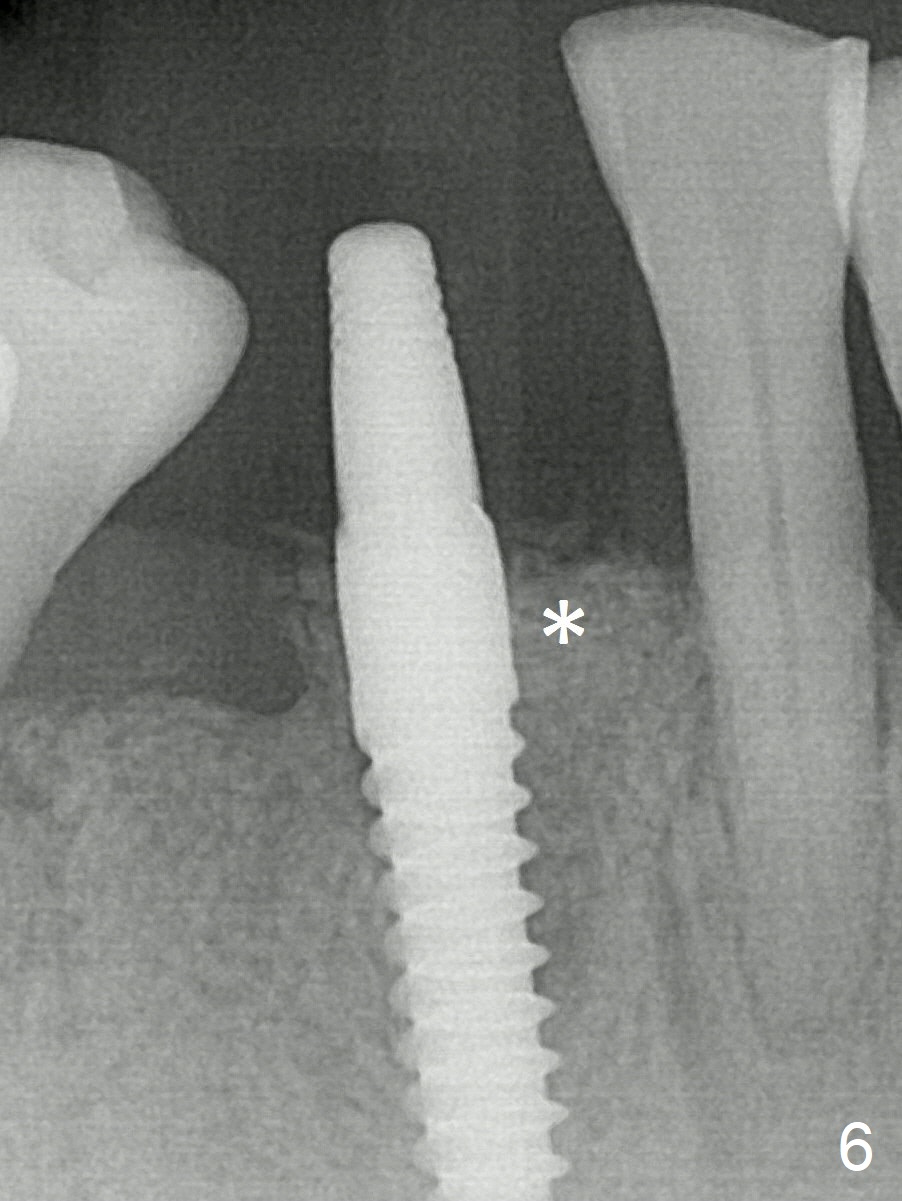

A 3x16(2) mm 1-piece implant is being placed as distal as possible (Fig.5 with 45 Ncm) with the mesial gap (*). The latter is filled with bone graft (Fig.6 *). The implant threads are not exposed 3 months 1 week postop (Fig.12).